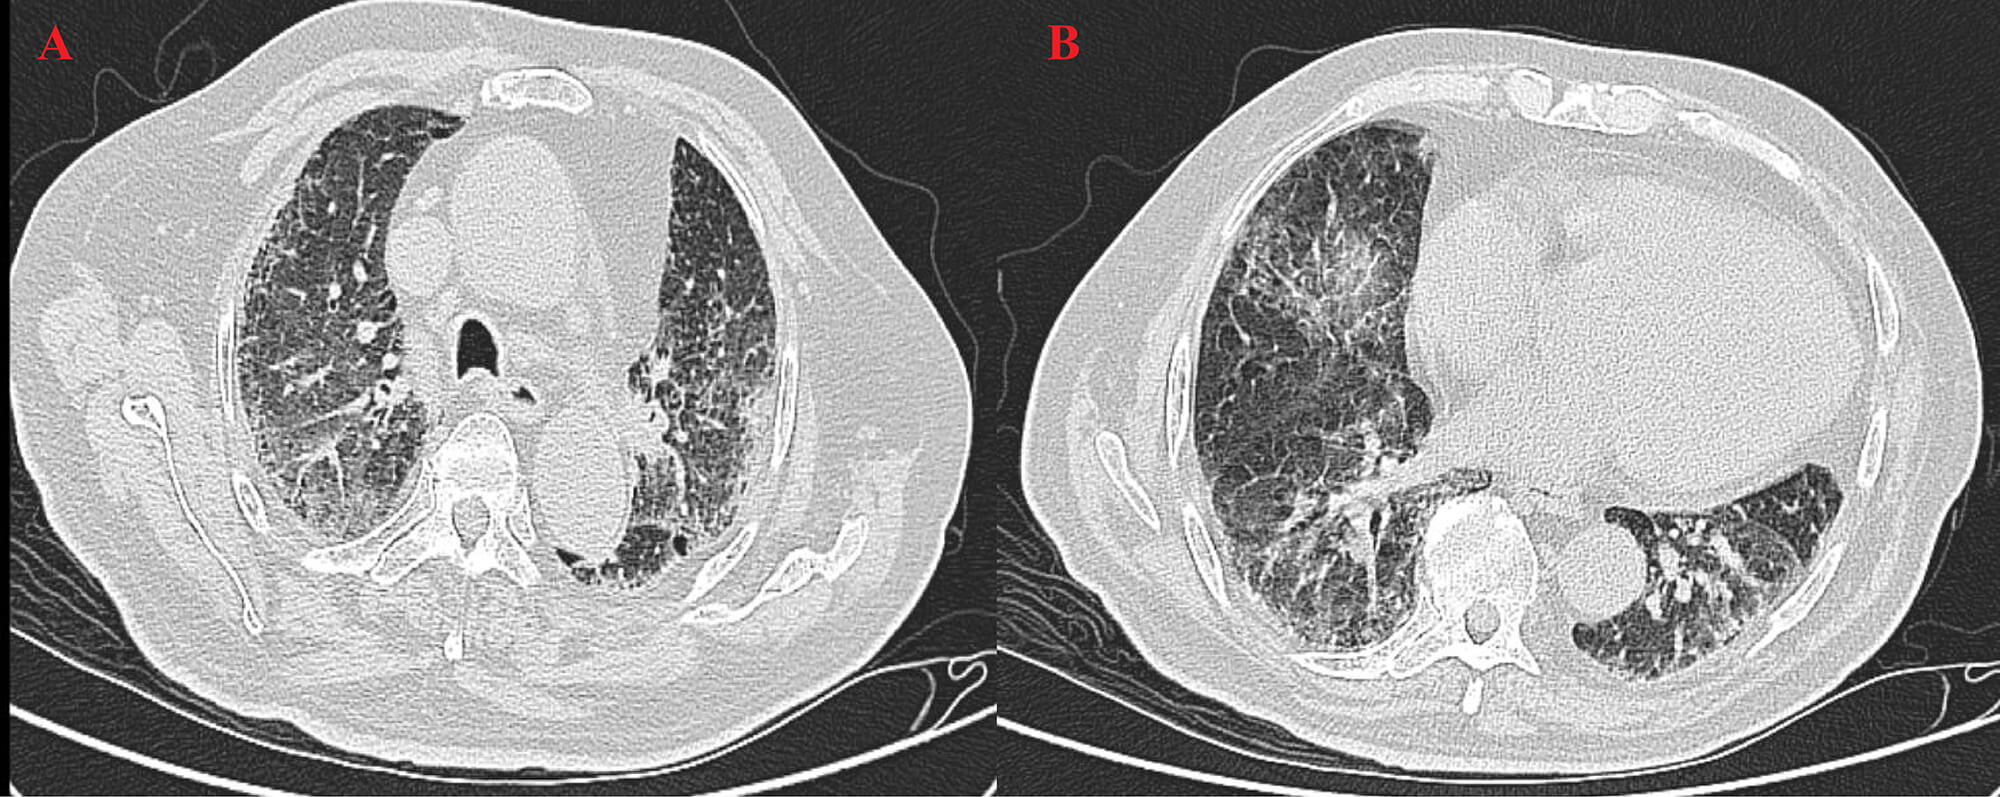

High-resolution computed tomography (HRCT) (Fig. 3) revealed patchy opacities in the left upper and right lower lobes, accompanied by multiple enlarged hilar and mediastinal lymph nodes (Fig. 4), interstitial inflammation in both lungs (Fig. 5), and a small pleural effusion. These findings were consistent with residual tumor and local progression following treatment for extensive-stage SCLC, demonstrating characteristic imaging features of SCLC.

Fig. 4.

HRCT on 6 May 2025. (A) The left upper lobe shows a patchy high-density shadow with interstitial changes, indicating post-treatment inflammation and tumor activity. (B) The right lower lobe shows consolidation with diffuse interstitial thickening and mediastinal lymphadenopathy, suggesting inflammatory progression.